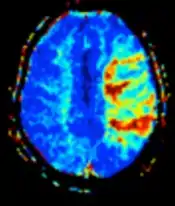

| Perfusion weighted (PWI) | Dynamic susceptibility contrast | DSC | Measures changes over time in susceptibility-induced signal loss due to gadolinium contrast injection.[80] |

|

![]() |